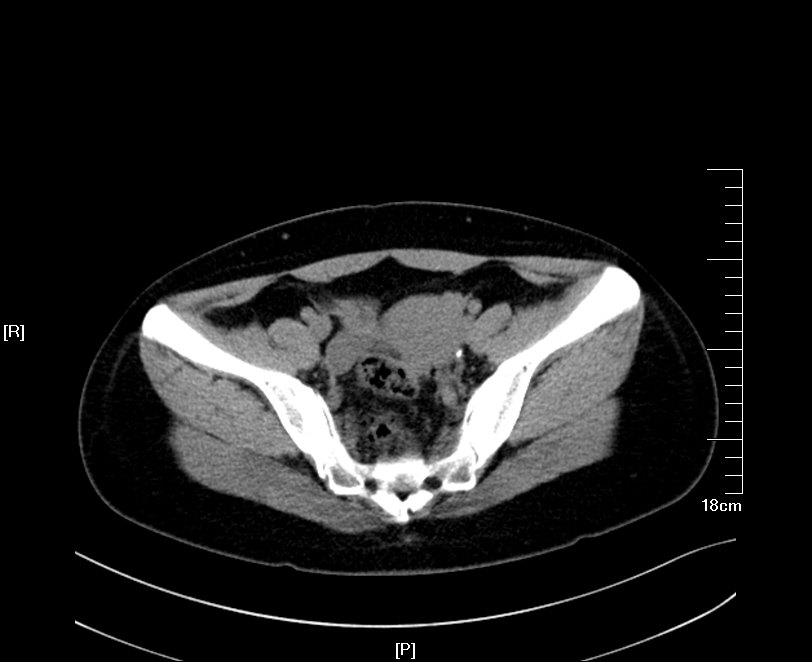

2016年09月手术患者,男性,83岁,太仓人,双侧腰酸不适五年伴体检发现双侧输尿管结石一周入院,五年来患者自觉双侧腰酸,一直未予重视,近期自觉双下肢浮肿且左侧腰痛明显加剧,遂参加社区免费体检时发现双侧输尿管结石遂来院就诊,CT:右肾萎缩无功能,左侧肾脏代偿性增大,左肾积水扩张,双侧输尿管结石,左侧约1.5cm,右侧约2.0cm GFR:左侧41.27ml/min,右侧5.2ml/min。肾功能:Cr 571umol/L;术前诊断:双侧输尿管结石 右肾萎缩 右肾无功能 左肾积水,鉴于右输尿管结石梗阻时间太长,右肾已几乎无功能,萎缩固缩,且肾功能已失代偿,遂只能急症先输尿管镜处理左输尿管结石,保护左侧肾脏,待肾功能稳定后再处理右侧输尿管结石及右肾,患者预后不容乐观。

CT检查提示:右肾萎缩无功能,左侧肾脏代偿性增大,左肾积水扩张,双侧输尿管结石